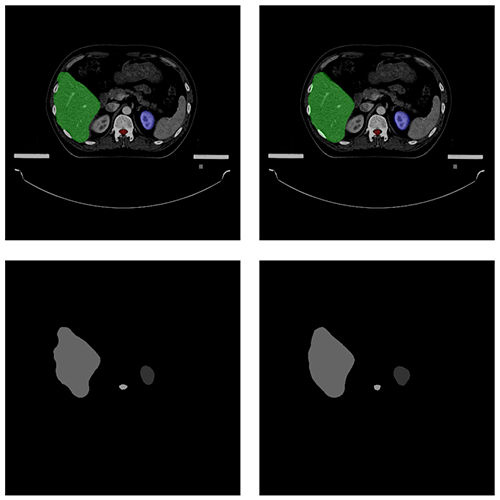

自動(dòng)勾畫效果

AUTOMATIC CONTOURING

原圖

預(yù)測圖